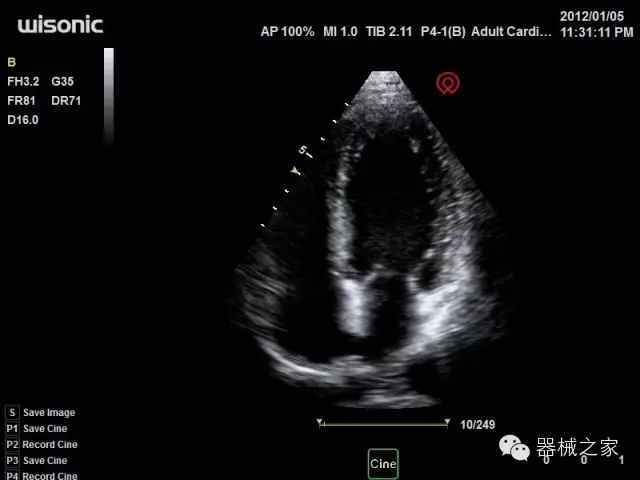

臨床圖片賞析

產(chǎn)品特點(diǎn)

·全球目前唯一一款配備主機(jī)雙探頭接口,整機(jī)重量(含電池)在5公斤以內(nèi)的便攜式彩超;

·心功能綜合指數(shù)(TEI指數(shù)):用于左、右心室整體心臟收縮舒張功能評(píng)估的測量方法;

·全方位可調(diào)M型:有利于更好的觀察心腔大小及室壁階段性運(yùn)動(dòng)的異常情況;

·組織多普勒成像(TDI):TDI可定量評(píng)價(jià)心肌運(yùn)動(dòng),判斷是否有局部病變,還可評(píng)價(jià)早期的舒張功能;